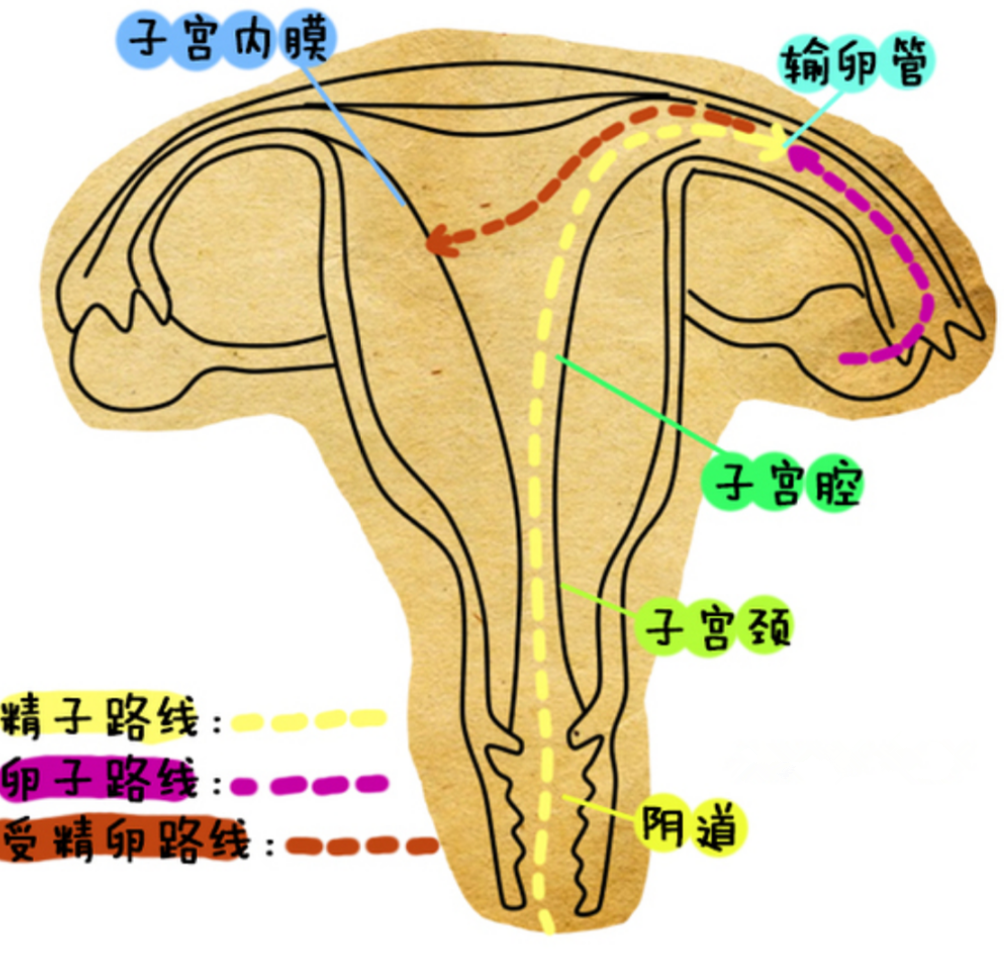

人工陰道漫畫的

人工陰道漫畫